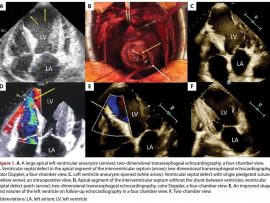

Read MoreReferring to the discussion on effective methods of treatment for patients with a post-infarction left ventricular aneurysm and a ventricular septal defect (VSD) [1], we present the case of a..

Read MoreLearning points: Hydatidosis or cystic echinococcosis is caused by infection with the metacestode stage of the tapeworm Echinococcus (family Taeniidae). The adult tapeworm is usually found in dogs or other..